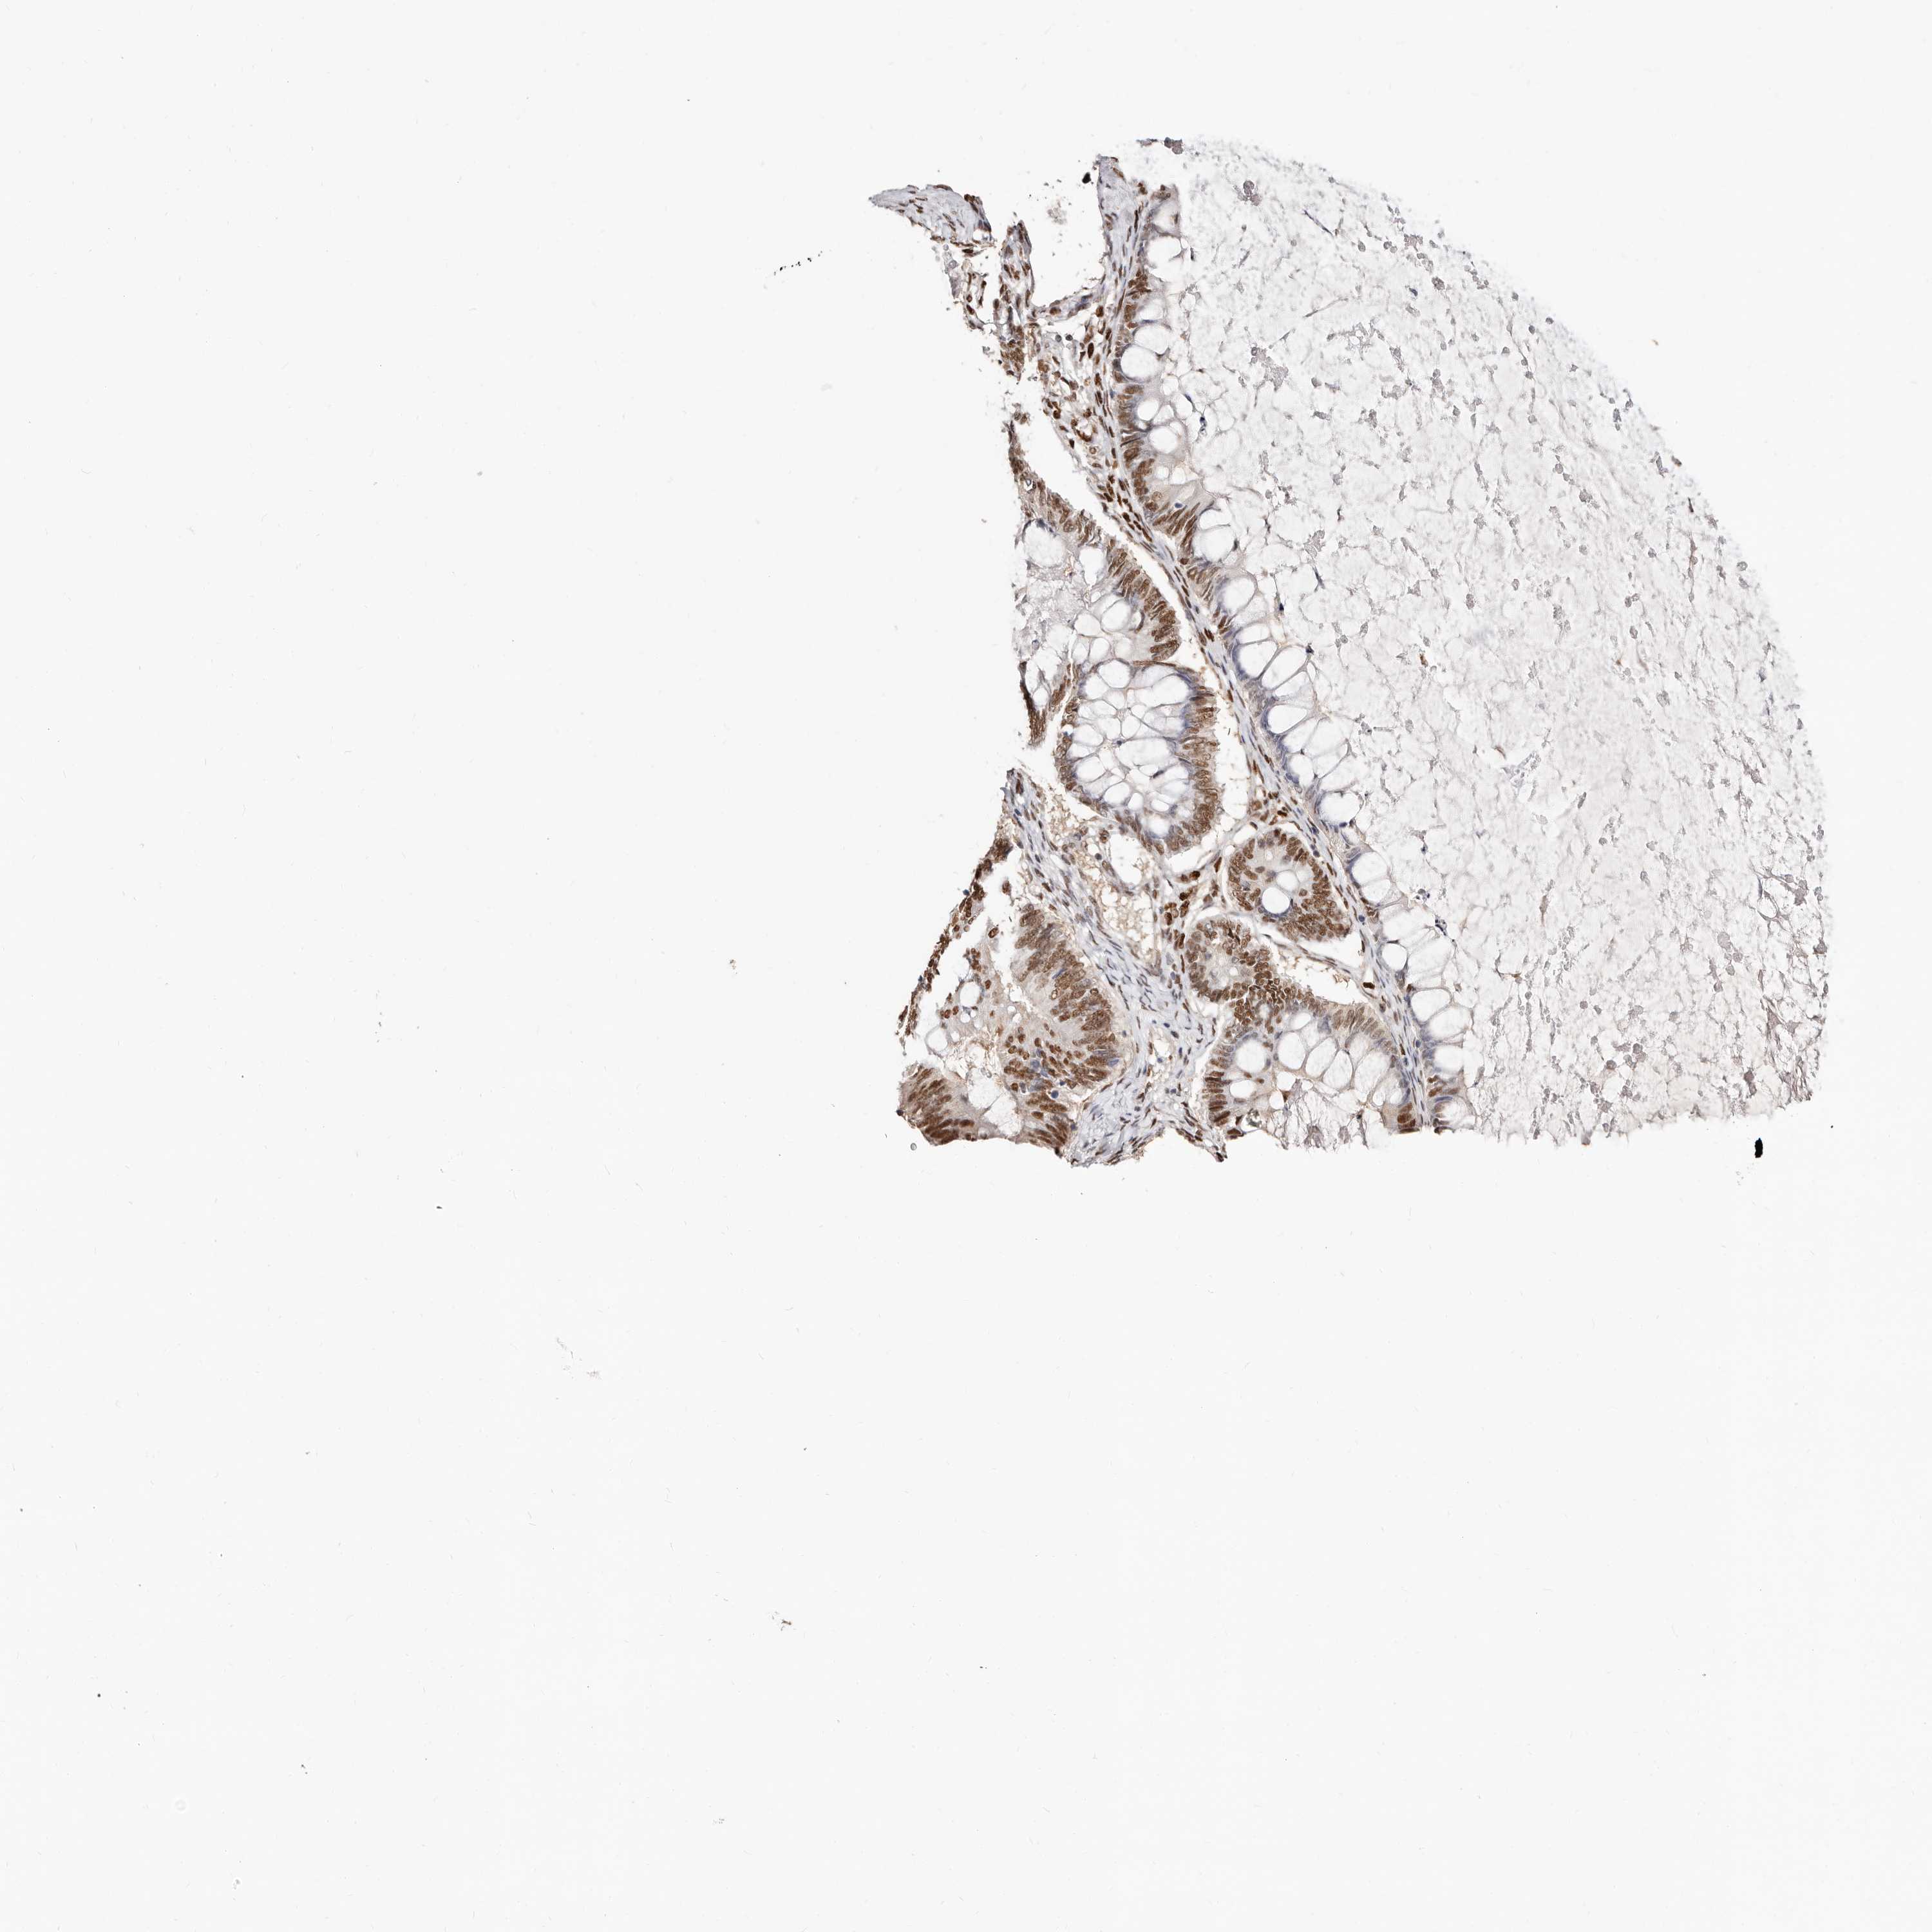

OVARIAN CANCER - Protein expressioni

A mouse-over function shows sample information and annotation data. Click on an image to view it in a full screen mode. Samples can be filtered based on level of antibody staining by selecting one or several of the following categories: high, medium, low and not detected. The assay and annotation is described here.

Note that samples used for immunohistochemistry by the Human Protein Atlas do not correspond to samples in the TCGA dataset.

Antibody stainingi

Antibody staining in the annotated cell types in the current human tissue is reported as not detected, low, medium, or high, based on conventional immunohistochemistry profiling in selected tissues. This score is based on the combination of the staining intensity and fraction of stained cells.

Each image is clickable and will lead to virtual microscopy that enables deeper exploration of all samples and also displays staining intensity scores, fraction scores and subcellular localization as well as patient and tissue information for each sample.

Antibody HPA029480

Antibody HPA029481

Cystadenocarcinoma, serous, NOS

Carcinoma, endometroid

Cystadenocarcinoma, mucinous, NOS

Carcinoma, NOS